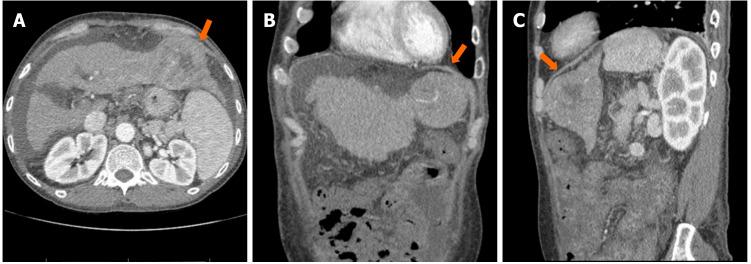

A 62-year-old male with chronic fasting hypoglycemia secondary to end-stage hepatitis C-related cirrhosis, presented with altered mental status and dizziness. He was found to have severe hypoglycemia refractory to glucose supplements. Imaging studies and biopsy discovered well differentiated HCC without metastasis. Further evaluation showed low insulin, C-peptide and beta-hydroxybutyrate along with a high insulin-like growth factor-2/insulin-like growth factor ratio, consistent with the diagnosis of NICTH. As patient was not a candidate for surgical resection or chemotherapy, he was started on prednisolone with some improvements in the glucose homeostasis, but soon decompensated after a superimposed hospital acquired pneumonia.

一名62岁男性,因丙型肝炎相关终末期肝硬化继发慢性空腹低血糖,出现精神状态改变和头晕。发现他患有严重低血糖,补充葡萄糖难以纠正。影像学检查和活检发现高分化HCC且无转移。进一步评估显示胰岛素、C肽和β-羟基丁酸水平低,同时胰岛素样生长因子-2/胰岛素样生长因子比值高,符合NICTH的诊断。由于患者不适合手术切除或化疗,开始使用泼尼松龙治疗,血糖稳态有一些改善,但在并发医院获得性肺炎后很快病情恶化。